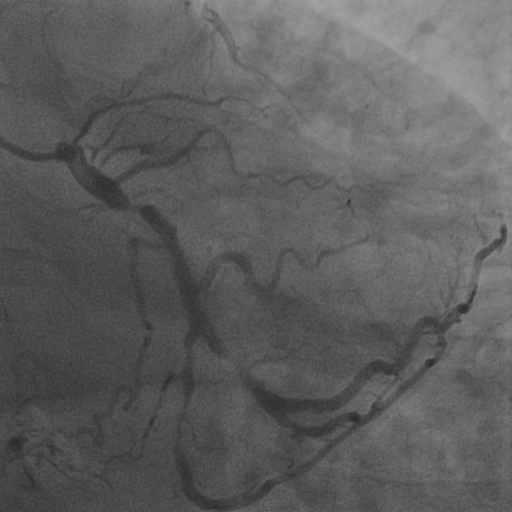

4.1 XACV Dataset

We collect 111 complete records of coronary artery X-ray videos from 59 patients, encompassing the injection, flow through the blood vessels around the heart, and dissipation of the contrast agent. Subsequently, we establish the XACV (X-ray Angiography Coronary Video) dataset. Each video consists of an average of 86 frames of high-resolution coronary artery X-ray images, with an equal distribution of left and right coronary arteries. We invite experienced radiologists to annotate the vascular regions, focusing on one or two frames where the contrast agent is most prominent in each video. These annotations are used only for evaluation in our method, not for training, maintaining the unsupervised nature of our approach. The data collection protocol involves several key steps, including patient preparation with informed consent and metal object removal, image capture using a Philips Allura Xper FD20 machine for standardized frontal (PA) and lateral views, DICOM file storage, and de-identification for patient privacy. Experienced radiologists perform diagnostic annotations using standardized tools and methods, with multiple annotations to enhance accuracy. Quality control measures, secure data management, and strict adherence to ethical guidelines and privacy regulations are implemented throughout the process. The XCAD dataset contains only a single image, and the CADICA video dataset does not provide corresponding ground truth. Therefore, in the following experiments, we conduct all the analyses on our collected XACV dataset and the corresponding GT for each sequence. In Figure 5, we show that compared to other publicly available datasets, XCAD (Ma et al., 2021) and CADICA (Jiménez-Partinen et al., 2024), our dataset exhibits finer annotations in the vascular regions, providing an advantage for future related tasks. The development and use of our dataset have been approved by our institution’s IRB. We will make the XACV dataset publicly available.